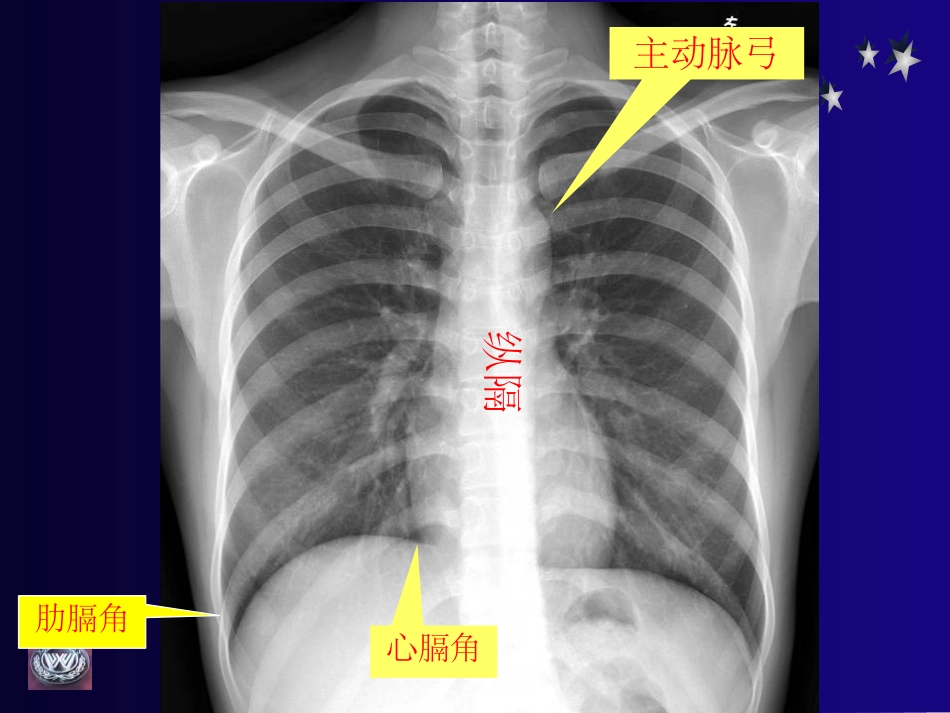

影像诊断基础摄影(平片)1、后前位:首选标准位置(正位胸片)2、侧位:解决前后定位及纵隔、横膈所遮掩部分3、前后位(仰卧位):用于床边胸片、肺底积液等肋膈角心膈角纵隔主动脉弓后胸壁后肋膈角前肋膈角浸润型肺结核X线表现:锁骨上下区可见片絮状密度不均影,边缘模糊,有时可形成不规则空洞,空洞内一般无液体。继发性型肺结核浸润型肺结核继发性型肺结核浸润型肺结核结核愈合后钙化继发性型肺结核肺内孤立性肿块的诊断观察要点:肿块的大小、数目、位置、密度、边缘,有无空洞、钙化及伴随改变。1、结核球:X线表现:•单发,类圆形结节影•直径多为2-3cm,•有层状、环形或斑点样钙化•点状、索条样卫星灶继发性型肺结核继发性型肺结核外围型肺癌:肺段以下,细支气管以上X线表现:•肺内单发结节影,大小不定。•肿块为类圆形、分叶状、少数为圆形,•边界清晰或有短毛刺。•密度大多均匀,钙化少见。•肿块内可有不规则空洞。外围型肺癌周围型肺癌外围型肺癌周围型肺癌周围型肺癌MRI扫描软组织分辨率高任意角度直接扫描骨骼、钙化显示差椎管内占位骨关节病变影像诊断比较平片:整体观察较好,软组织结构差CT:髓腔显示好,软组织内结构清楚,可发现小病变MR:软组织结构最佳,多角度观察易发现病变全身骨骼不规则骨脊柱正常颈椎脊柱·颈椎腰椎腰椎解剖基本病变X线表现骨质疏松是指一定单位体积内正常钙化的骨组织减少,即骨组织的有机成分和钙盐都减少,但骨内的有机成分和钙盐含量比例仍正常。X线表现1.骨密度减低2.骨小梁减少清晰3.骨皮质变薄骨质软化是指一定单位体积内骨组织有机成分正常,而钙盐含量降低。X线表现1.骨密度减低2.骨小梁和骨皮质模糊3.骨骼变形骨质破坏正常骨组织被病理组织所代替X线表现1.局限性骨密度减低2.骨小梁稀疏或骨质缺如3.骨皮质破坏甲状腺癌肱骨转移CT平片T1WI骨质增生单位体积内骨量增多X线表现1.骨密度增高2.骨小梁增多增粗3.骨皮质增厚4.骨骼增粗髓腔闭塞骨膜增生骨膜内层成骨活动增加所引起的骨质增生X线表现骨膜反应:与骨皮质平行葱皮样花边状与骨皮质垂直放射状骨质坏死局部血液中断,骨质缺血,代谢停止X线表现死骨出现见于:急慢性骨髓炎缺血性坏死骨结核股骨头缺血性坏死周围软组织病变肌肉、肌间隙和皮下脂肪异常常由外伤、感染、软组织肿瘤引起X线表现1.软组织肿胀2.软组织层次模糊不清,密度增高,3.外伤后骨化性肌炎腰大肌肿胀胸椎结核矢T1WIT2WI冠T1WI周围软组织病变骨质坏死骨膜增生骨质增生骨质破坏骨质软化骨质疏松基本病变X线表现颈椎病临床表现:颈部疼痛,活动受限,疼痛可向肩及患侧上肢放射。由于病变多发生在颈5-6及颈6-7椎间隙,因此主要为臂丛神经受损的表现,并可有根性感觉障碍。颈椎正位颈椎侧位颈椎右斜位颈椎左斜位颈曲变直颈椎轻度增生颈椎骨质增生颈椎病颈椎病颈椎病腰椎退行性变临床表现主要症状为腰腿痛,约占全部患者的95%以上,多数为单侧,腰腿痛同时发生,并向下放射,常因咳嗽、打喷嚏或排便加重。腰椎棘突旁有局限性压痛,严重者可出现下肢麻木,运动障碍和肌肉萎缩。正常腰椎腰椎正常斜位正常椎间盘膨出椎间盘突出环状纤维完整椎间盘突出环状纤维被穿破后纵韧带完整游离的间盘碎片腰椎退行变腰椎退行变正常椎间盘及椎管腰椎间盘脱出腰椎间盘脱出腰椎间盘变性椎小关节骨质增生关节破坏关节软骨及骨性关节面被病变组织侵犯X线表现1.关节间隙变窄2.骨端骨破坏和骨缺损3.关节半脱位和变形左髋关节结核关节的基本病变关节肿胀关节破坏关节退行变关节强直关节脱位关节退行变在骨端的关节软骨变性坏死和溶解X线表现1.骨性关节面模糊、中断、消失2.关节间隙变窄3.软骨下骨质囊变和骨性关节面边缘骨赘形成类风湿脊柱炎竹节椎矿质沉积铅、氟进入体内过多,成骨活跃,骨量增加,破骨活动也增加。X线表现1.骨密度增高2.骨小梁增粗紊乱石骨症